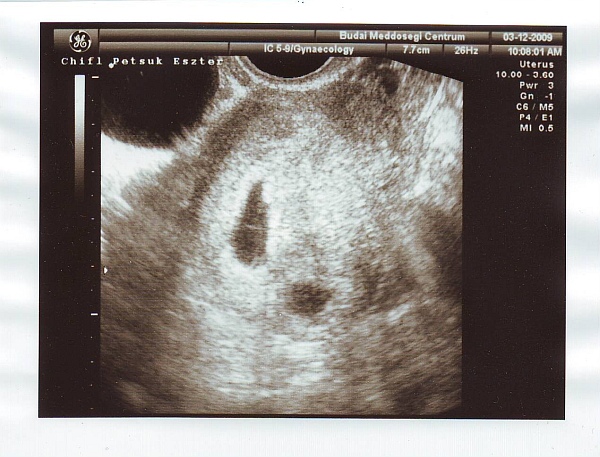

Az én 7 hetes sztárfotóm hüvelyivel készült! De én nem vinném be a páromat!!!!!!!!

Jeanner, dehogynem lehet, a kép nem attól függ, milyen uh volt! Megmutizzam Sacit öthetesen? ;)

mi ilyenek voltunk 5 hetesen (ekkor még 4 lánykánk volt, de csak kettőről tudtunk)

Úgyhogy kb erre számíts az 5 hetes hüvelyi uh-n! :)